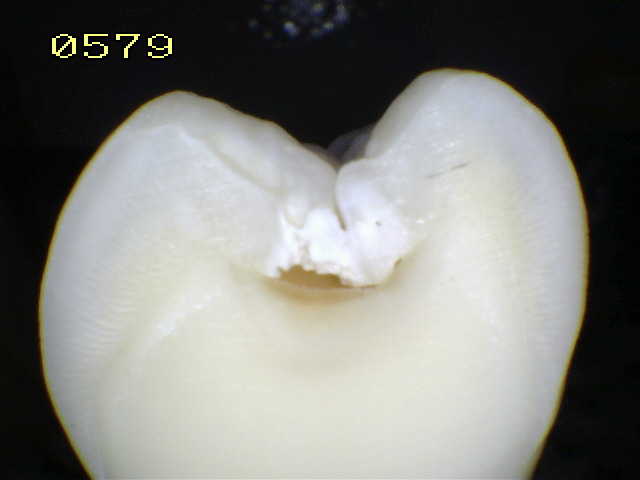

Espécimen 5 |

|

| Corte sagital |

Verificando un código 1 histológico |

Espécimen Nº 14 |

|

Corte sagital |

Verificando un

código

1 histológico |